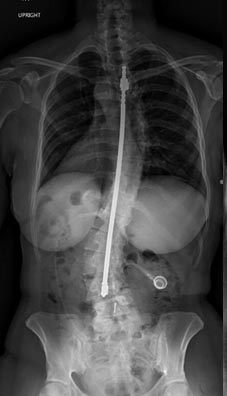

59 year old woman with Scholiosis with severe back pain.

1 year postop from surgery and pain free.